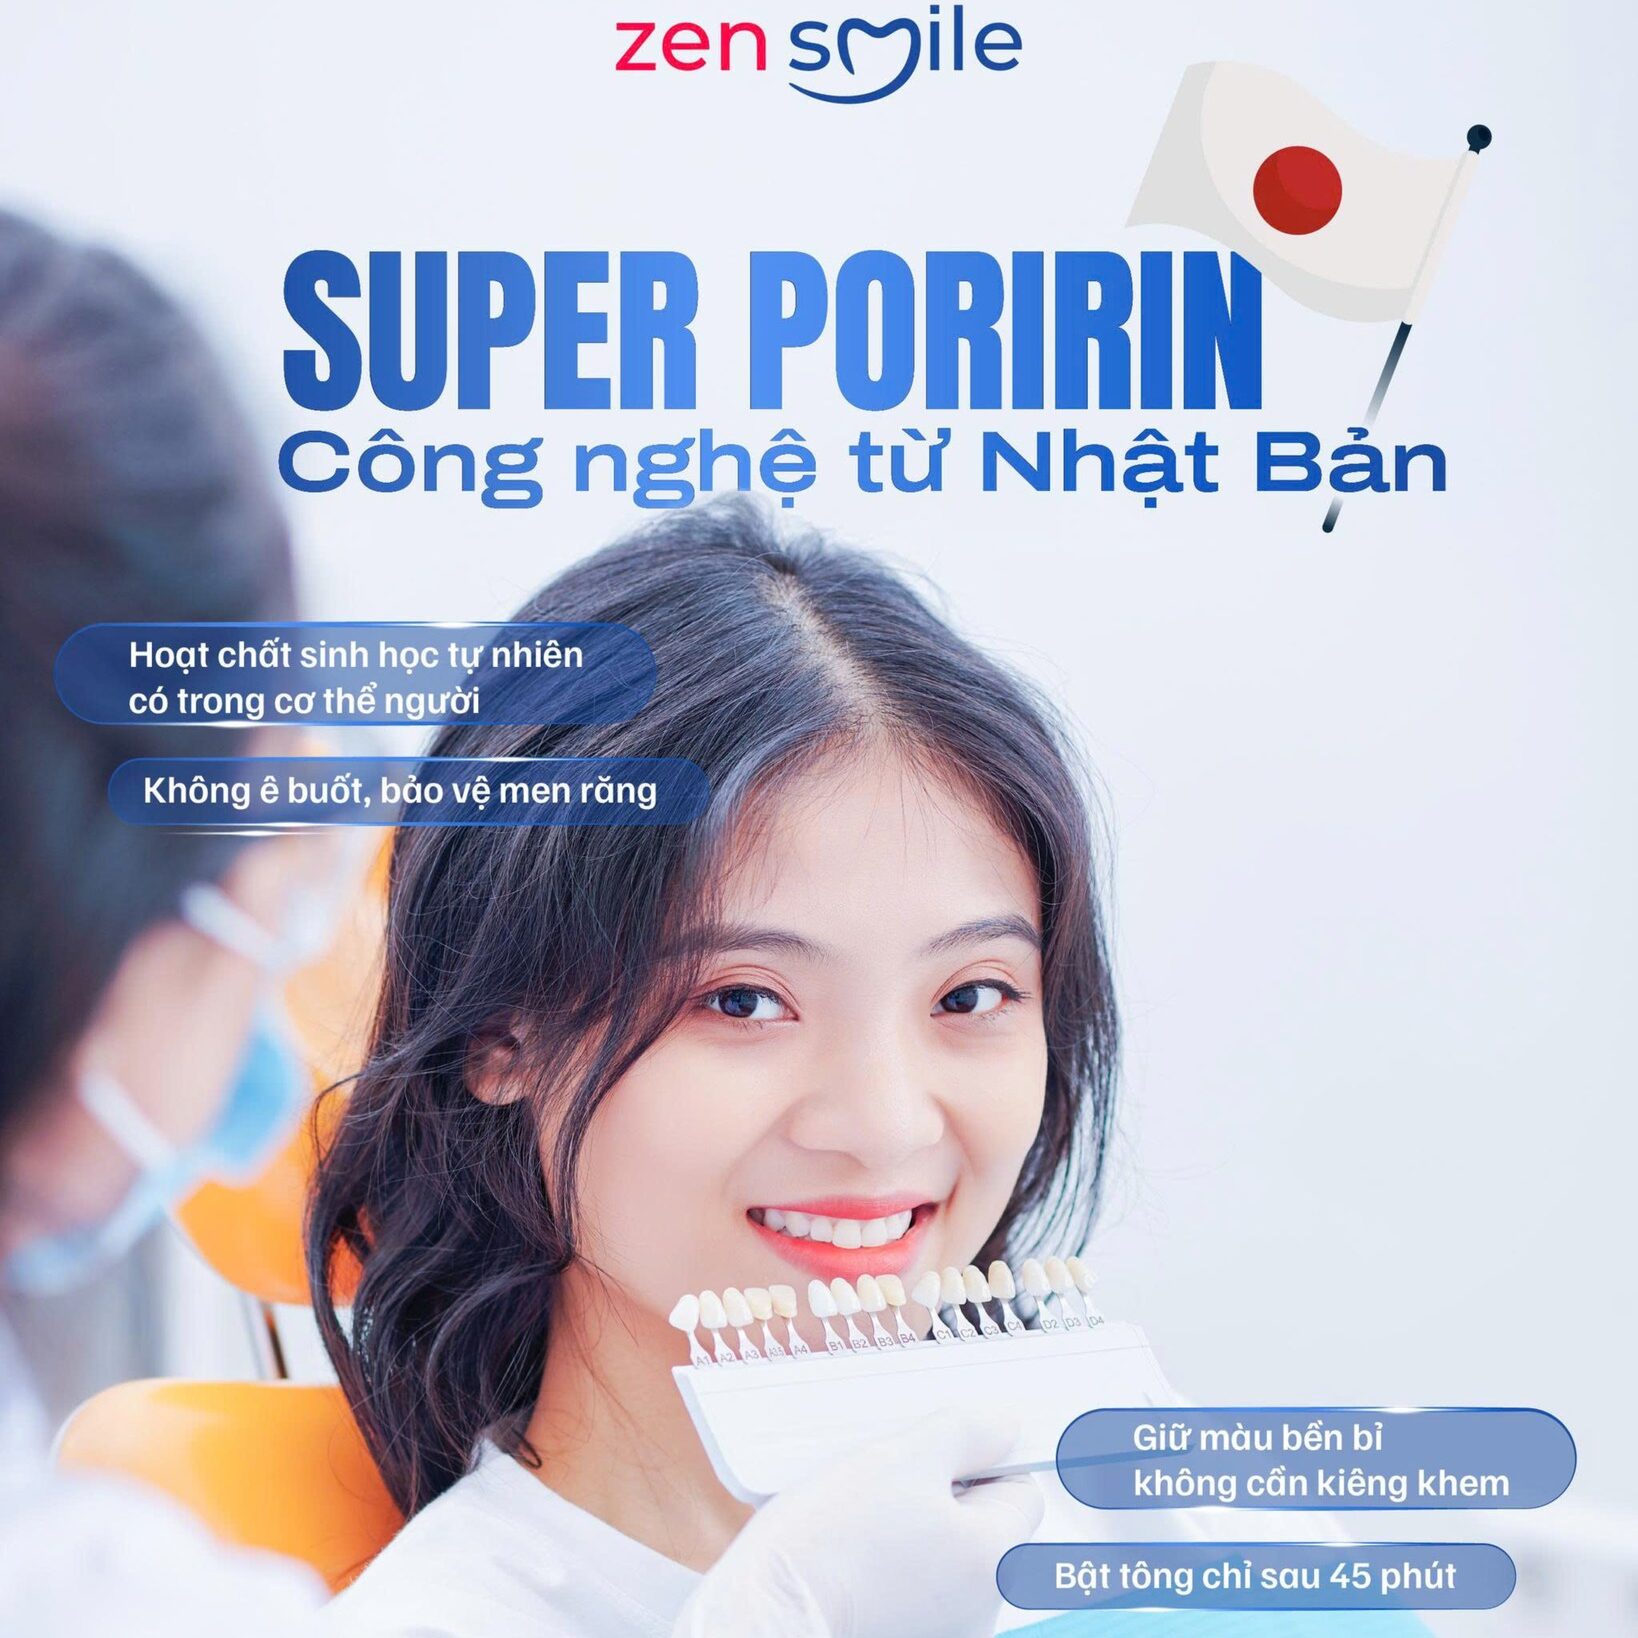

Tại Zensmile, chúng tôi ứng dụng công nghệ tẩy trắng răng ánh sáng xanh thế hệ mới, giúp phá vỡ các phân tử gây nhiễm màu sâu trong cấu trúc men răng, từ đó phục hồi màu trắng sáng tự nhiên của răng một cách an toàn và hiệu quả.

Phương pháp này hoạt động dựa trên sự kết hợp giữa năng lượng ánh sáng xanh và thuốc tẩy chuyên dụng, giúp làm trắng răng từ bên trong, mang lại kết quả đều màu, trắng bật lên vài cấp độ chỉ sau một liệu trình.Toàn bộ quá trình được thực hiện trực tiếp bởi bác sĩ chuyên khoa Zensmile – đội ngũ giàu kinh nghiệm, được đào tạo bài bản về tẩy trắng răng chuyên sâu. Quy trình đảm bảo an toàn tuyệt đối, không gây ê buốt, không tổn thương men răng và mang lại cảm giác thoải mái cho khách hàng trong suốt quá trình thực hiện

Trải nghiệm công nghệ tẩy trắng tuyệt vời này tại Nha Khoa Zensmile, bạn sẽ hoàn toàn thay đổi quan niệm về tẩy trắng răng vì Super Poririn chính là lựa chọn của những ai mong muốn sở hữu nụ cười trắng sáng và khoẻ manh.

Với Super Poririn, Nha Khoa Zensmile cam kết:

- KHÔNG Ê BUỐT

- KHÔNG BÁM DÍNH MÀU, TÁI Ố VÀNG

- KHÔNG BÀO MÒN MEN RĂNG

Đặt lịch tư vẫn miễn phí ngay tại Nha Khoa Zensmile – Chuẩn Y Khoa Quốc Tế